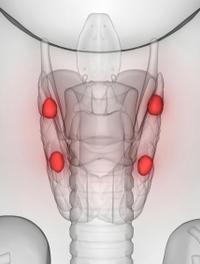

L’hyperparathyroïdie primaire (HPT1) est désormais parmi les maladies endocriniennes les plus fréquentes, en occupant la troisième [...]